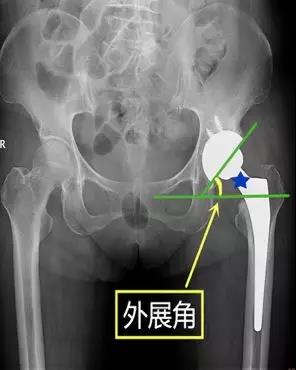

- 髋臼杯外展角:即在骨盆正位片上髋臼杯上缘和下缘连线与水平线的夹角。

- 正常值:45°~55°

- 临床意义:外展角过大容易发生髋关节内收时撞击,假体外上缘应力集中和髋关节不稳,并向后上方脱位。髋臼杯外展角>55°时,其股骨头假体受力方向由内上逐渐变化指向外上 ,脱位机率明显增加。

D’Lima等研究认为45°~55°的外展角对髋关节的活动度和稳定性来说是最合适的,在此范围内髋臼杯对股骨头的覆盖较好,与股骨头表面接触较多,应力分布均匀,关节稳定。